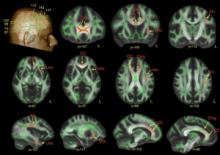

AUTISME: Des différences cérébrales subtiles identifiées chez les hommes atteints

Actualité publiée il y a 10 années 2 moisPSYCHO: Le bien-vivre son âge a un effet direct sur la santé